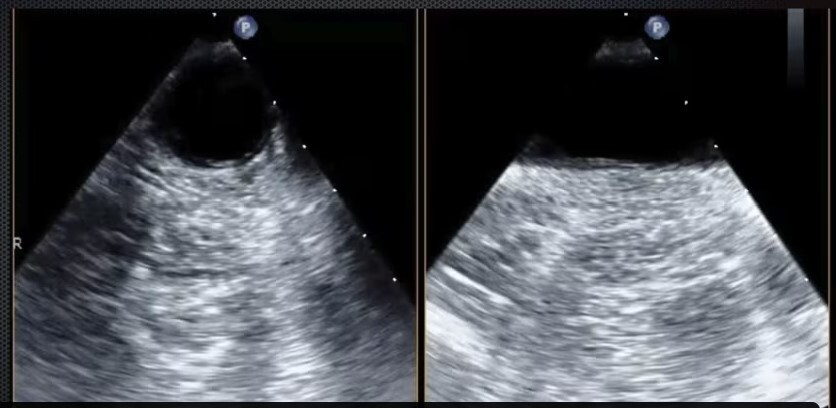

Mid-Esophageal 4 chamber view. Structures: R atrium, R ventricle, L atrium, L ventricle, anterior and posterior mitral leaflets. 30-35 cm into the esophagus. Turn R until you center on mitral valve. Plane to 10-20 degrees.

Mid-Esophageal 2 chamber view. Multiplane to between 80-100 degrees.

Structures: LA, LV, coronary sinus, L atrial appendage